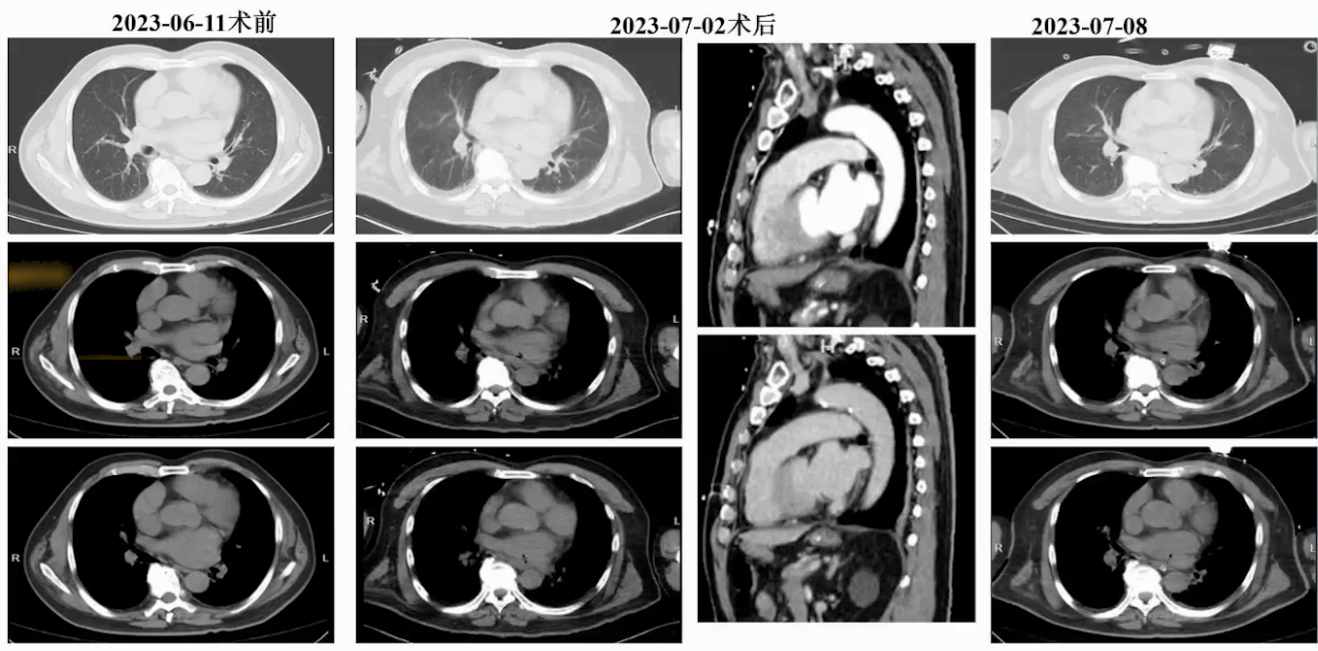

头颅CT:两侧额顶叶深部基底节区缺血灶,胸腹部CT未见明显炎性改变,头颅CTA示颅内动脉粥样硬化,左侧颈内动脉眼段少许钙化斑,局部管腔轻度狭窄,未见明显栓塞性改变。

心超复查显示双房增大,二尖瓣中度反流,三尖瓣轻度反流,房间隔可见细小左向右分流,主动脉瓣可见钙化、中度反流。头颅CT平扫示左侧小脑半球和左侧额顶叶缺血梗死灶可能,胸腹部CT未见明显炎性和栓塞病灶。此时,颅内栓塞来源(房颤血栓或心内膜炎菌栓)尚无法确定,因心内膜炎诊断不明确。

入院第5天复查,头颅CT发现两侧额叶基底节区和左侧小脑多发梗死灶,较前明显进展;床旁心脏超声发现在二尖瓣有5毫米赘生物随心动周期飘动,考虑颅内栓塞是心内膜炎感染引起的菌栓脱落所致。